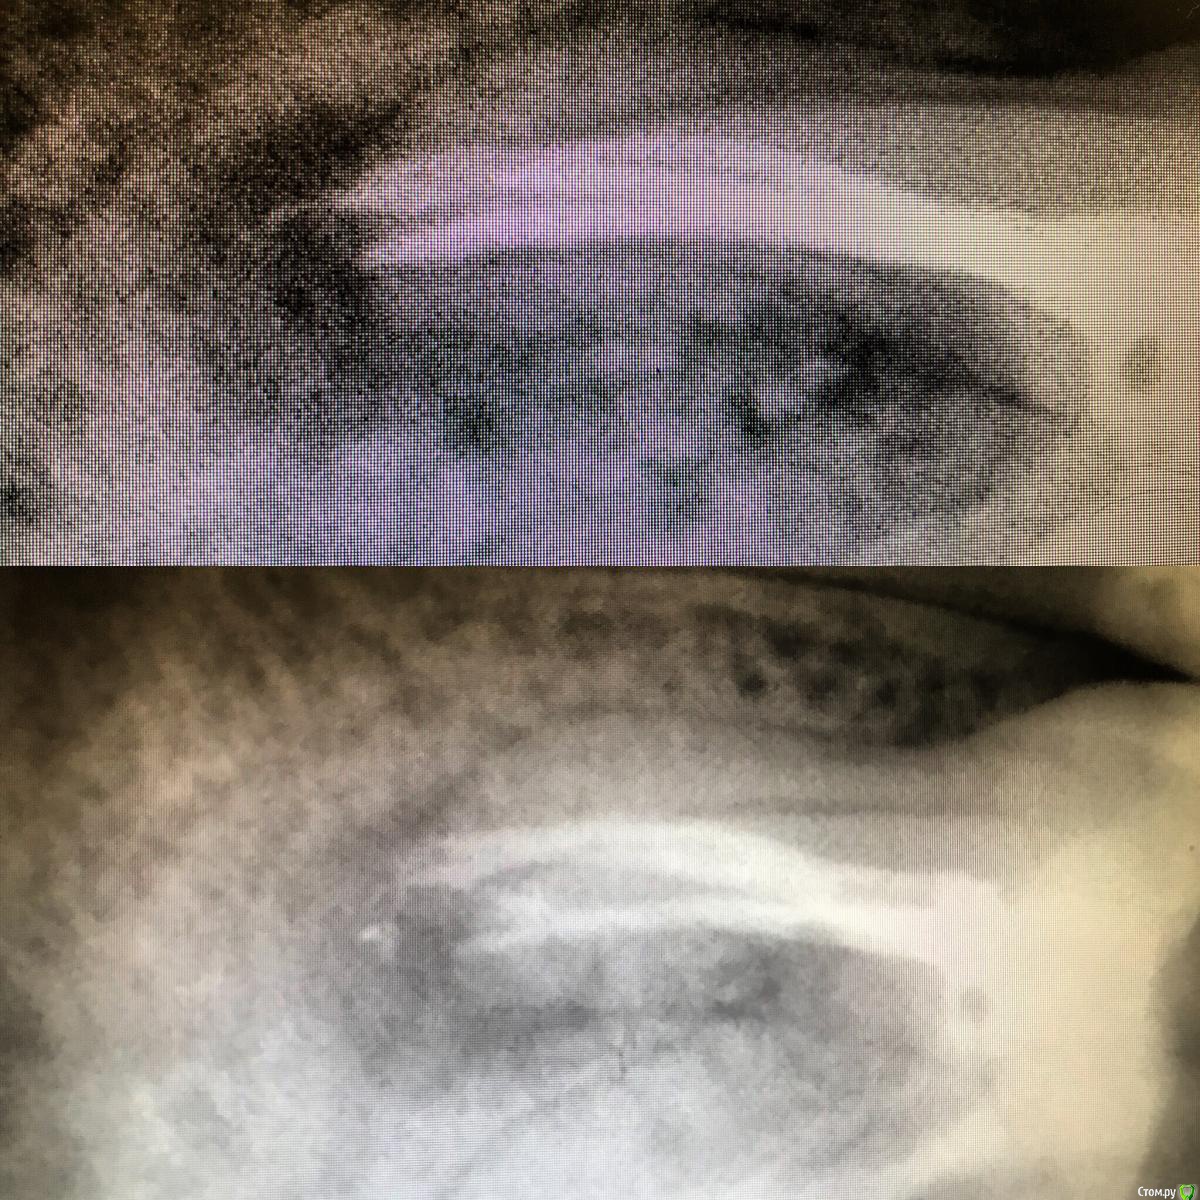

1586Doc Опубликовано 7 июня, 2019 Автор Поделиться Опубликовано 7 июня, 2019 все в кучу ) Ссылка на комментарий